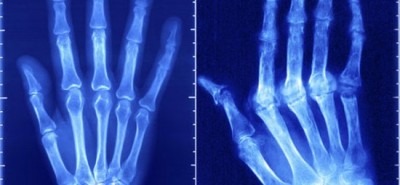

- Припухание суставных флангов указательного и среднего пальцев, лучезапястного сустава с признаками воспалительного процесса.

- Деформация суставов стоп рядом с основанием пальцев. Сопровождается болезненными ощущениями при нажатии на пальцы ног.

- Воспалительный процесс в крупных суставах при прогрессировании болезни (плечи, локти, колени). Иногда воспаление начинается именно с крупных суставов, а в последствии переходит на кисти рук.

- Возникновение узелков (плотные образования под кожей) в изгибах локтей, кистей.

Наглядная информация про артрит